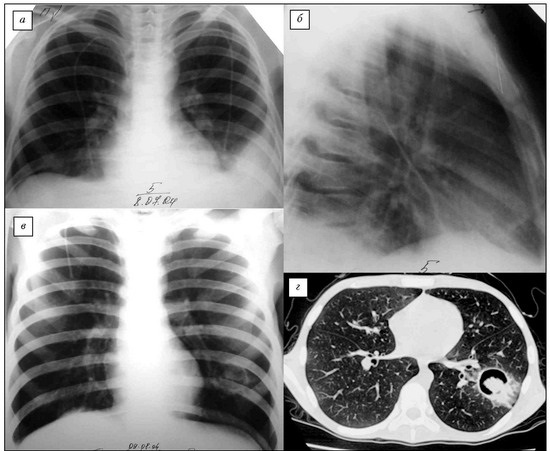

Рис. 6. Этапы развития инвазивного аспергиллеза легких. В течение 7 дней формируется полостное образование.

Рис. 10. КТ. Инвазивный острый аспергиллез легких. Множественные участки инфильтрации и полосные образования в легком.